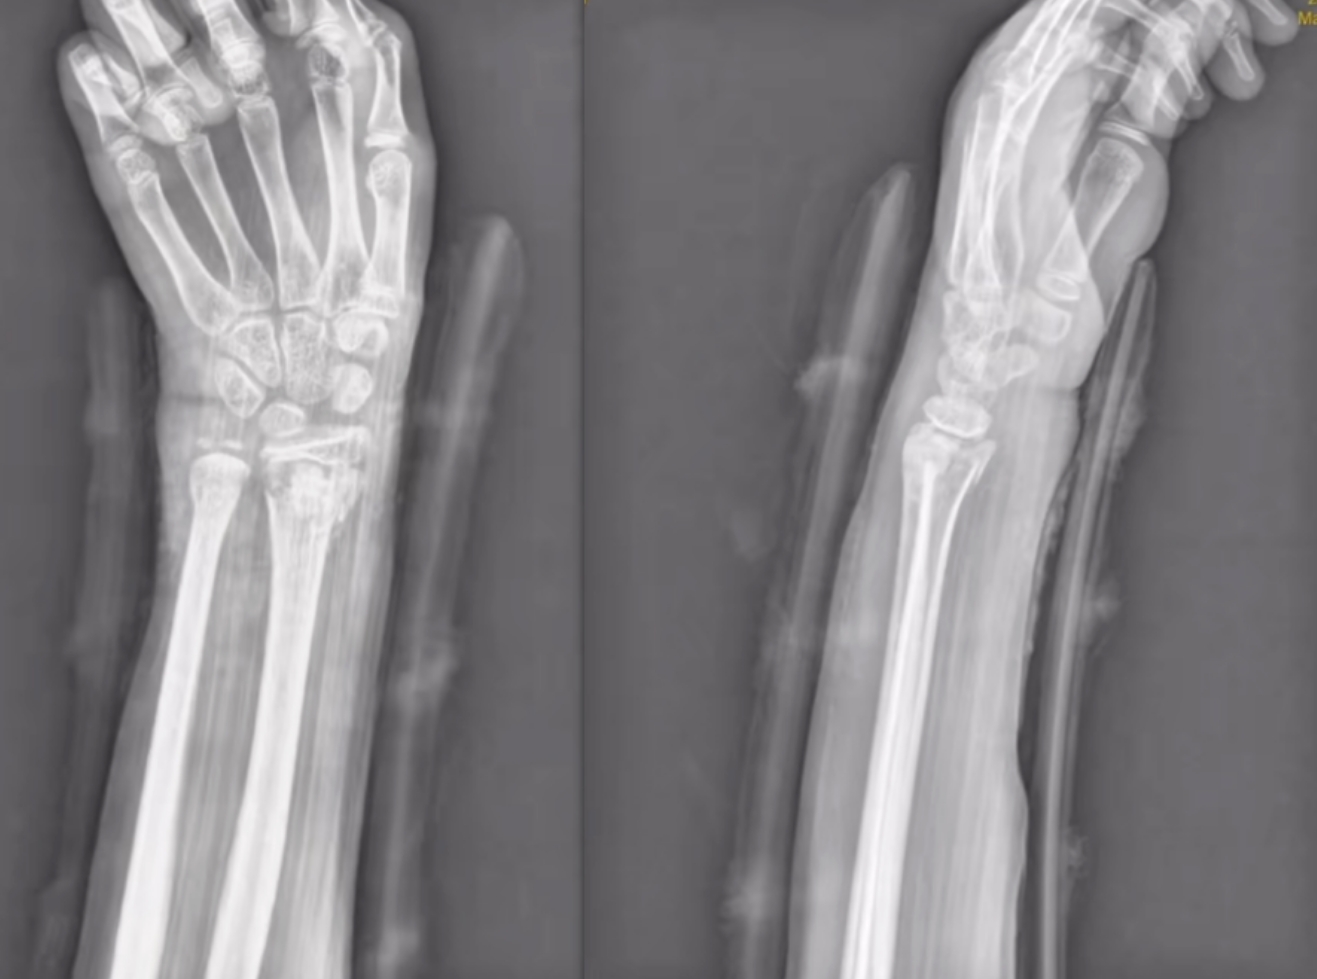

尺橈骨遠(yuǎn)端骨折復(fù)位前 尺橈骨遠(yuǎn)端骨折復(fù)位后